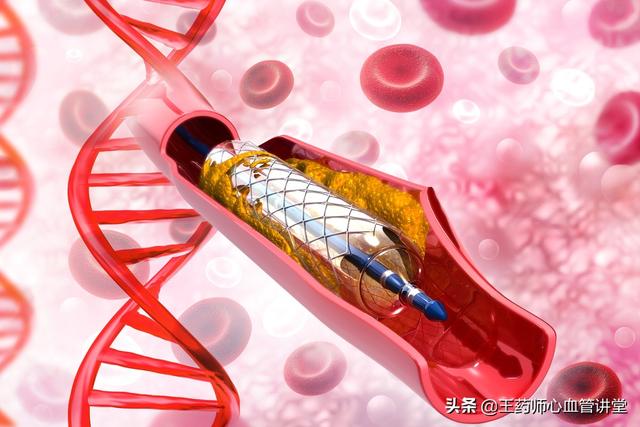

私たちは皆、多かれ少なかれ知っているはずだ。冠状動脈性心臓病とは、主に心臓の冠状動脈が狭くなる病気である。心臓に血液を供給する血管の狭窄は、心筋虚血や心筋壊死を引き起こす可能性があり、この狭窄を解消して冠動脈への血液供給を回復させるために、治療法のひとつは次のようなものである。何か支えとなるものを持っていく。それこそが、今、私たちが話しているブラケットなのだ。

ステップ3:軌道を確立する。最初のガイドワイヤーは冠動脈より太いので、この時は細いガイドワイヤーを選んで冠動脈病変の遠位部を通過させ、まずバルーンで拡張しなければならない。

ステップ4:ステントを留置する。バルーンの拡張が完了したら、このガイドワイヤーに従ってステントを留置する。

心臓ステント留置術は、閉塞した血管にステントを挿入し、閉塞を解除することで心筋への正常な血液と酸素の供給を回復させ、心臓の正常な機能を維持するインターベンショナル手技である。ステント留置術は心臓内で行われ、異物が挿入されるため、多くの患者さんがステント留置術の安全性を心配している。実際、過度の心配は不要である。

第二に、ステント留置術そのものについては、患者は過度に心配する必要はない。ステント留置術は大病の部類に入るが、それ自体は成熟した手段であり、腫瘍摘出や臓器移植などの他の手術に比べ、成功率が高く、安全性も確実である。ステント留置術は低侵襲手術であり、人体への外傷も少なく、また、循環器科の手術の中で最も一般的なものであることから、ステント留置術はすでに極めて成熟した手術であり、専門病院で専門医が行う限り、成功率は絶対的に保証される。ステント留置の心配については、実はその必要はない。現在、臨床で使用されているステントのほとんどは、コバルト、クロム、ニッケルなどの合金製で、組織適合性に優れ、拒絶反応やアレルギーのリスクはない。さらに、ステントは時間とともに血管壁に埋め込まれ、血管と一体化していくので、患者がステントの位置ずれやズレを心配する必要もない。したがって、手術もステント自体も比較的安全である。